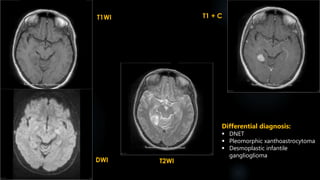

DNET

 Dysembryoplastic neuroepithelial tumor- benign, focal, intracortical mass superimposed on

background of cortical dysplasia

 vast majority are centered in cortical grey matter, arise from secondary germinal layers

 C/F- longstanding partial complex seizures

 Age- < 20 years

 Site - temporal lobe ( amygdala/ hippocampus) 60%, frontal lobe 30%, caudate nucleus,

cerebellum and pons

DNET (contd.)

DNETs are typically predominantly cortical and well circumscribed tumours.

 CT:

 if cortical may scallop the inner table of the skull vault (44-60%), but no erosion

 the cranial fossa can be minimally enlarged at times

 calcification in ~30% (more common histologically)

 low density; no enhancement

 MRI:

 T1 - generally hypointense c.f adjacent brain

 T1 C+ (Gd) - may show enhancement in ~20-30% of cases; enhancement may be heterogeneous

or a mural nodule; focal punctate or ring enhancement- 20%

 T2 - generally high signal; high signal 'bubbly appearance‘

 FLAIR- hypo/ isointense with bright rim; no peritumoral edema

 DWI- lacks restricted diffusion

Differential diagnosis:

 Ganglioglioma

 Pleomorphic xanthoastrocytoma

 Pilocytic astrocytoma

 Desmoplastic infantile ganglioglioma

 Oligodendroglioma

 Choroid fissural cyst

 HSE and limbic encephalitis

 Mesial temporal sclerosis